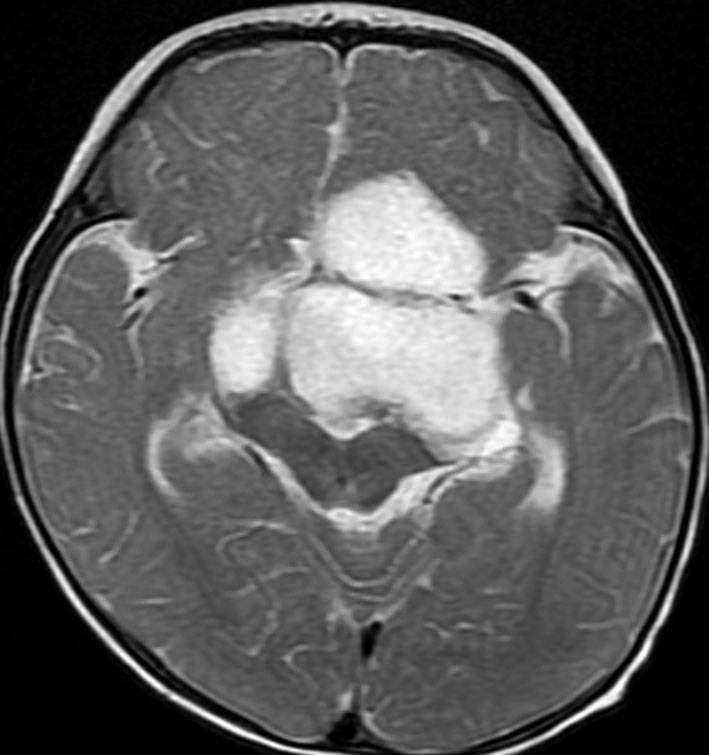

幼児の視路の毛様粘液性星細胞腫です。T2強調画像(左側)で白く高信号に写るのが特徴です。ガドリニウム増強ではまだらになっていますが,均一に真っ白に高信号になることも多いです。乳幼児のものは,ドロドロに柔らかい腫瘍です。

- 大きな腫瘍では,第3脳室上部のモンロー孔の閉塞のために閉塞性水頭症となり嘔吐や意識障害で発症することもあります

3. 視路視床下部毛様細胞性星細胞腫 optic pathway / hypothalamic pilocytic astrocytoma

最も多い重要なタイプで,主として視交叉から視床下部へも浸潤するものです

化学療法抵抗性,あるいはのう胞性拡大などの場合によって,減荷手術 debulking surgery のタイミングが難しいものです

乳幼児時期には,病理組織像が毛様粘液性星細胞腫で,MRI T2で均一な高信号になりガドリニウムで強く増強されます。腫瘍の増大速度は速く,稀には髄液播種することもありそれが腫瘍死の原因となることもあります。奏効率の高い化学療法を早く開始する必要があります。

少し経過して幼児期には,速度は落ちるがやはり腫瘍は増大傾向をたどり腫瘍内のう胞形成とのう胞の拡大をみることが多いでしょう。この時期にも症状の悪化が多く,化学療法は継続する必要があります。pilomyxoid typeからjuvenile type pilocytic astrocytomaへ病理組織像が変わっていきます。

学童期では,化学療法が奏効すれば腫瘍の増大が止まるか,あるいはまたゆっくりと再増大します。それとは別に,腫瘍実質が増大せずに,腫瘍のう胞のみが拡大するという現象が生じます。のう胞拡大は oncolytic cyst と呼ばれるような腫瘍変性に伴うものであり,化学療法を行なってものう胞拡大を止めることが難しいです。手術によるのう胞壁部分摘出がとなる時期でもあります。